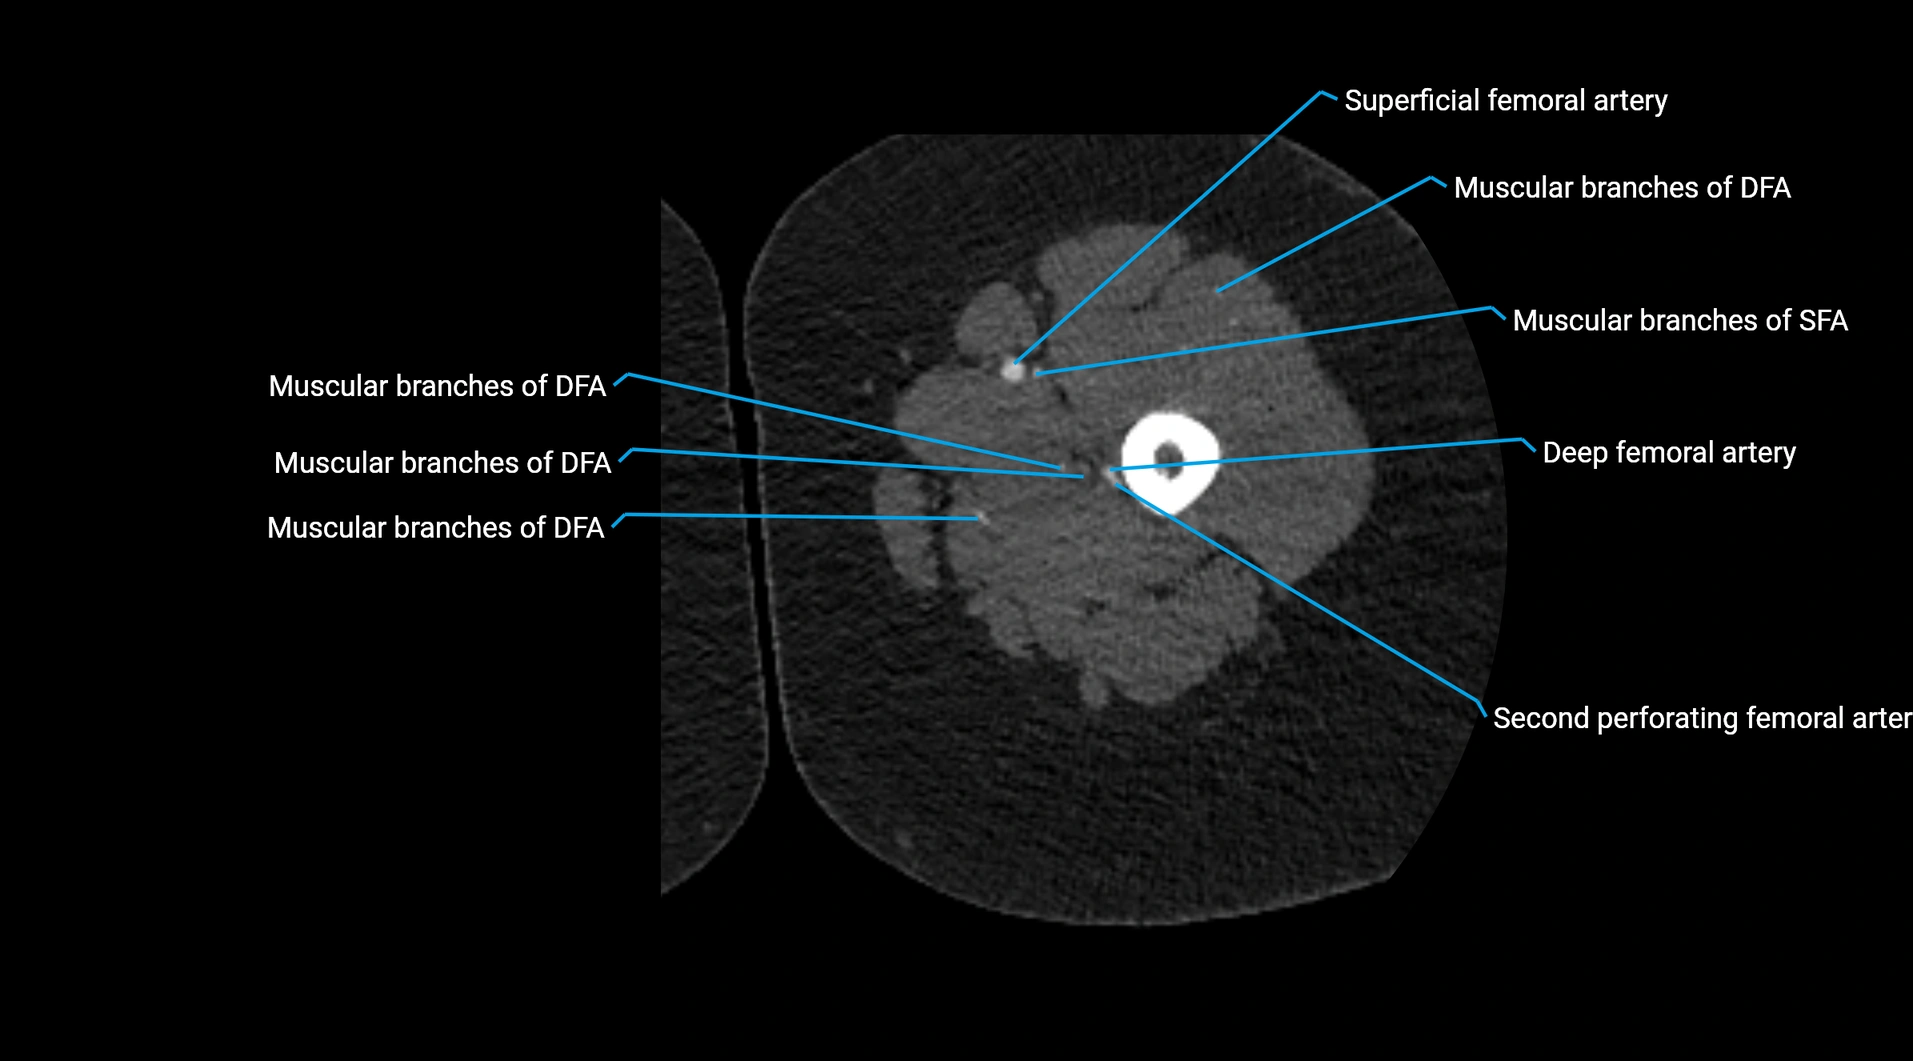

Contrast-enhanced CT (CTA):

• Gold standard for abdominal aortic imaging

• Provides excellent detail of lumen, wall, aneurysm, thrombus, and branch vessels

• Multiplanar and 3D reconstructions help in aneurysm measurement, stent graft planning, and dissection evaluation

• Detects acute rupture, traumatic injury, or occlusion with high sensitivity